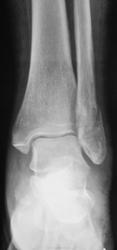

Пол пациента: Мужской пол Тип патологии: Травма Область исследования: Скелетно-мышечная система Методы исследования: Rg Травма. Пациент направлен на рентгенографию голеностопного сустава. https://radiomed.ru/sites/default/files/styles/case_slider_image/public/user/12/2.p4180015.jpg?itok=-HTogZ0n ID:21012 Пнд, 30/04/2012 - 13:14 #1 doktor-rentgen Не на сайте Был на сайте: 9 лет 2 месяцев назад Зарегистрирован: 06.07.2010 - 20:56 Публикации: 640 Перелом латеральной и задней(краевой перелом) лодыжки. А что за очаги просветления в метадиафизе б/б кости? Пнд, 30/04/2012 - 19:16 #2 Дмитрий К Не на сайте Был на сайте: 6 лет 5 месяцев назад Зарегистрирован: 27.10.2011 - 10:17 Публикации: 120 + перелом пяточной кости Пнд, 30/04/2012 - 21:18 #3 doktor-rentgen Не на сайте Был на сайте: 9 лет 2 месяцев назад Зарегистрирован: 06.07.2010 - 20:56 Публикации: 640 Дмитрий К wrote: + перелом пяточной кости Ткните где перелом, пожалуйста Втр, 01/05/2012 - 00:12 #4 Александр Викторович Не на сайте Был на сайте: 8 лет 2 недели назад Зарегистрирован: 31.07.2010 - 13:05 Публикации: 639 doktor-rentgen wrote: Дмитрий К wrote: + перелом пяточной кости Ткните где перелом, пожалуйста пятка цела Втр, 01/05/2012 - 13:52 #5 surgeon23 Не на сайте Был на сайте: 13 лет 6 месяцев назад Зарегистрирован: 25.04.2012 - 17:09 Публикации: 69 задний край и латеральная лодыжка. Пятка целая перемены - это единственное постоянство, которое нам дано Втр, 01/05/2012 - 20:54 #6 Катенёв Валенти... Не на сайте Был на сайте: 7 лет 4 недели назад Зарегистрирован: 22.03.2008 - 22:15 Публикации: 54876 surgeon23 wrote: задний край и латеральная лодыжка. Пятка целая Да, "кусочек" от задней лодышки не отвалился, но перелом есть.

Перелом латеральной и задней(краевой перелом) лодыжки. А что за очаги просветления в метадиафизе б/б кости?

задний край и латеральная лодыжка. Пятка целая

Да, "кусочек" от задней лодышки не отвалился, но перелом есть.